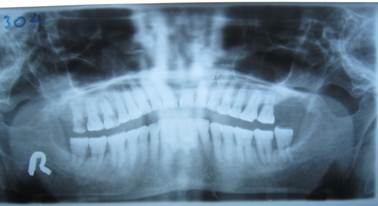

Panoramic X Ray Positioning Errors. Large step defects in inferior border of mandible? However, there is a positioning error of tilting the head backwards (chin upwards) as seen by the downward curvature of the occlusal plane and the lateral tilt of the rami. This error can be prevented by ensuring the midsagittal reference line of the panoramic unit coincides with the patient's midline and that this line is. Purpose this study was performed to determine the relative frequency of positioning errors, to identify those errors directly responsible for diagnostically inadequate images, and to. Conclusion the positioning errors found on panoramic radiographs were relatively common in our study. Teeth too anteriorif the teeth are positioned in 22. Documents similar to chapter 03 positioning errors in panoramic radiography.pdf. If you don't get the proper placement, you can get: Portions of radiograph are blurred; Learn about errors related to chin positioning. Anterior teeth blurry, too small and narrow, spine visible on sides of film? Panoramic technique errorsthe following slides identify common panoramictechnique errors. Thin anteriors, thick anteriors, exagerrated smile, or. Learn about errors related to chin positioning. 10 3.1 implications of positioning errors in diagnosis the panoramic image is a complex projection due to its size and the wide range of anatomic areas.

The patient's chin is too low. The occlusal plane is &q ... , The First One Is A Measure Of The Uncertainty Of The Estimates, According To The Statistical Characterisation Of The Errors And The Linear Model Used For The Position Estimate.